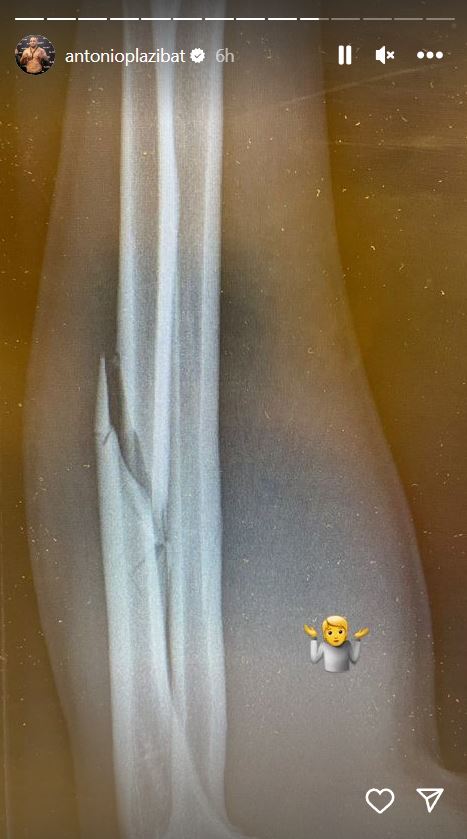

Plazibat je nakon poraza, odlaska u bolnicu i snimanja na rendgenu pokazao pratiocima na društvenim mrežama mesto na kojem mu je ruka pukla! Očigledno je nigerijski borac znao gde da napadne Antonija, pa mu je snažnim udarcima po rukom polomio taj deo tela i odmah nakon borbe ga naterao u bolnicu, a pored toga mu napravio i dodatne probleme.

Hrvatski kikbokser Antonio Plazibat polomio ruku tokom meča

Foto: Instagram/antonioplazibat/printscreen